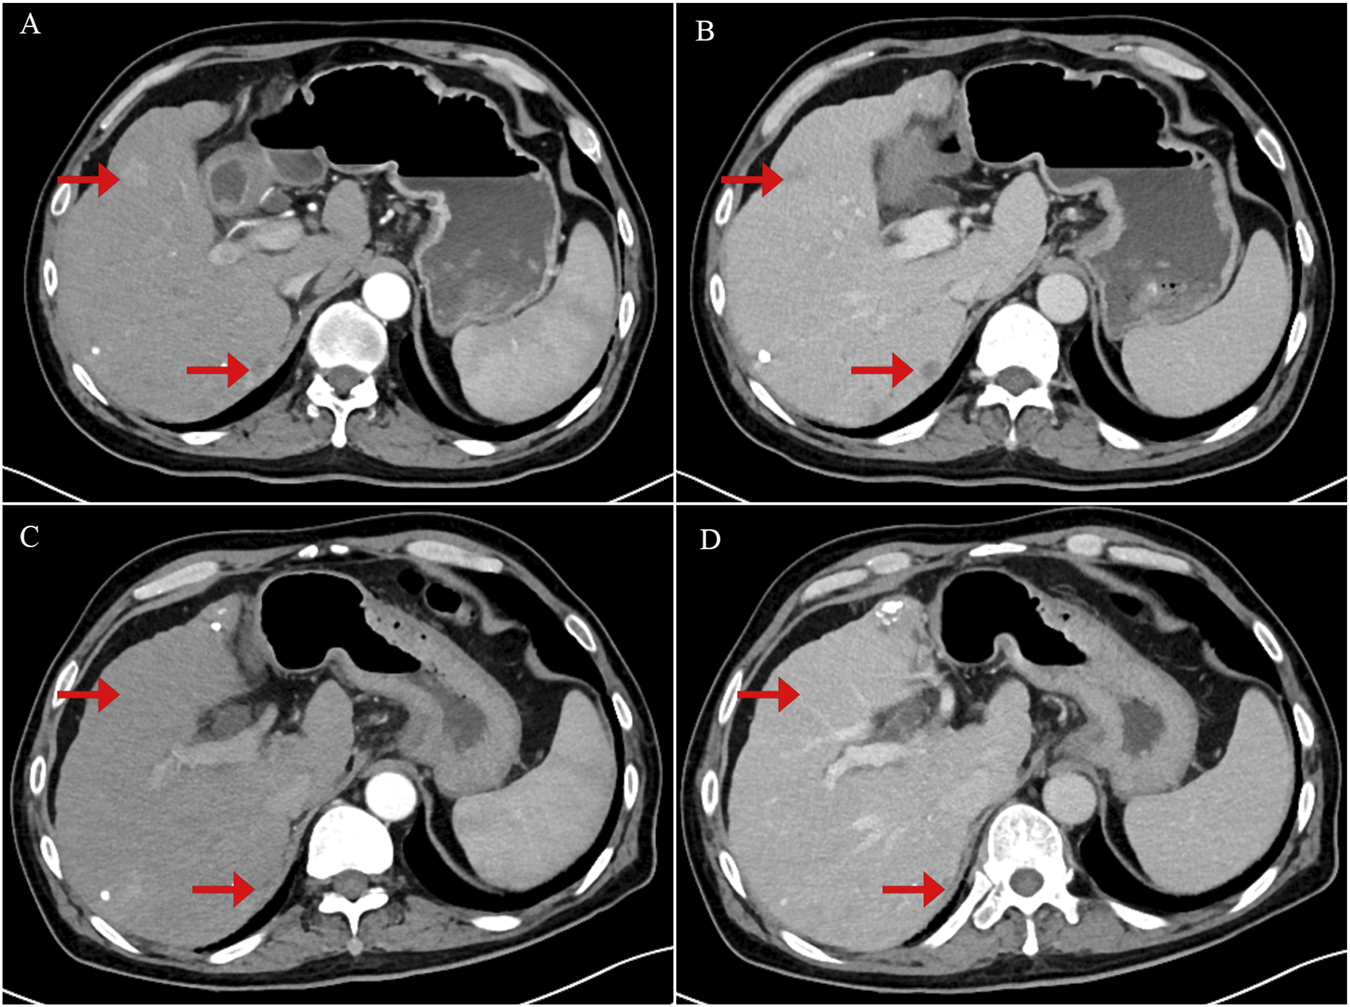

FIGURE 2

Contrast-enhanced abdominal computerized tomography (CT) scan images showing tumor recurrence and treatment response following crizotinib therapy. (A) Arterial phase image demonstrating a strongly enhancing nodule consistent with tumor recurrence. (B) Portal venous phase image showing persistent but slightly decreased enhancement of the lesion. (C) Arterial phase image obtained 1 month after initiation of crizotinib therapy, showing tumor shrinkage and reduced arterial enhancement of the nodule. (D) Portal venous phase post-treatment image demonstrating further tumor shrinkage with near-complete resolution of nodule enhancement.

A 56-year-old male with a more than 20-year history of chronic hepatitis B virus infection and liver cirrhosis was diagnosed with HCC in May 2019. The diagnosis was based on an elevated serum alpha-fetoprotein (AFP) level of 51 ng/mL and characteristic imaging findings that revealed a hepatic mass (Figure 1). The patient underwent a laparoscopic left lateral lobectomy, with the pathological diagnosis confirming moderately to highly differentiated HCC. The pathological findings were previously reported in an earlier publication (Gu et al.). In October 2020, local recurrence was detected, and the patient received radiofrequency ablation (RFA). Despite receiving multiple systemic therapies—initially lenvatinib plus camrelizumab, followed by sorafenib, and subsequently regorafenib in combination with sintilimab—as well as various local interventions including transcatheter arterial chemoembolization (TACE) and stereotactic body radiotherapy (SBRT), the disease progressed. Notably, vertebral metastases led to spinal cord compression and paraplegia. Given the advanced progression, next-generation sequencing (NGS) was performed and revealed MET gene amplification with a copy number of 30.2 (Table 1). Consequently, crizotinib was initiated at a dosage of 200 mg/day on 24 January 2022. This resulted in significant clinical and radiological improvement, including marked tumor regression, normalization of AFP and protein induced by vitamin K absence-II (PIVKA-II), and stable hepatic and renal function. Subsequent imaging demonstrated substantial reduction of tumor burden, with complete remission of certain lesions (Figure 2).